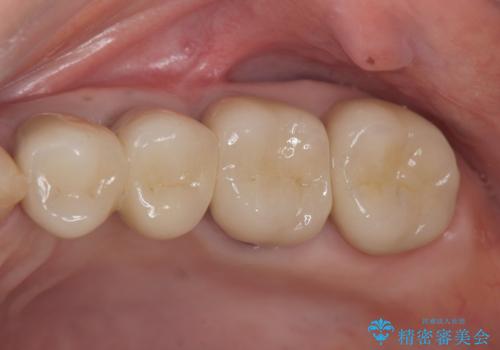

銀歯や古くなったクラウンをやりかえたい

X線写真検査ではわからない虫歯も外してみると再発していることがあります。虫歯を丁寧に取り除き、再発を防ぐべく精密なクラウンの作製を行うことが長期的な予後につながります。